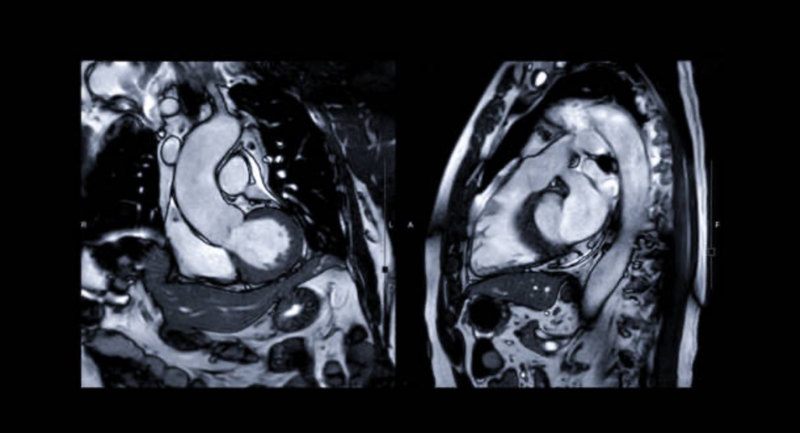

Cardiac MRI

A cardiac MRI (cardiovascular MRI or CMR) is a non-invasive imaging technique that uses magnetic fields and radio waves to create detailed images of the heart and blood vessels, aiding in the diagnosis and monitoring of various heart conditions.

What is Heart MRI?

What it can show?

- Heart structure: Chambers, valves, and blood vessels.

- Heart function: How well the heart pumps blood.

- Heart muscle: Damage or disease in the heart muscle.

- Blood flow: Assessing blood flow to and from the heart.

- Other conditions: Tumors, inflammation, and other heart-related issues.

Why it’s used?

- Diagnosis: To help diagnose various heart conditions, including congenital heart disease, heart muscle disease, heart valve disease, and coronary artery disease.

- Monitoring: To monitor the progression of heart conditions and assess the effectiveness of treatments.

- Planning: To help doctors plan for surgeries or other interventions.